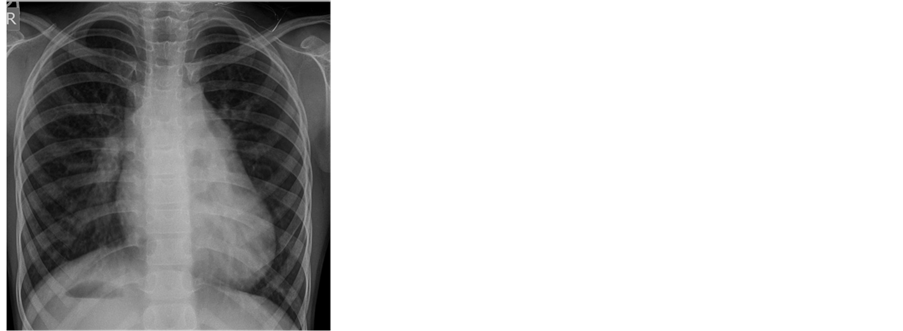

A posteroanterior chest radiograph demonstrated normal position of the heart, cardiomegaly, pulmonary plethora and right-sided gastric air bubbles (Figure 1). An electrocardiogram (ECG) indicated left ventricle (LV)

Figure 1. Chest X-ray showing cardiomegaly with pulmonary plethora and right-sided gastric air bubbles.